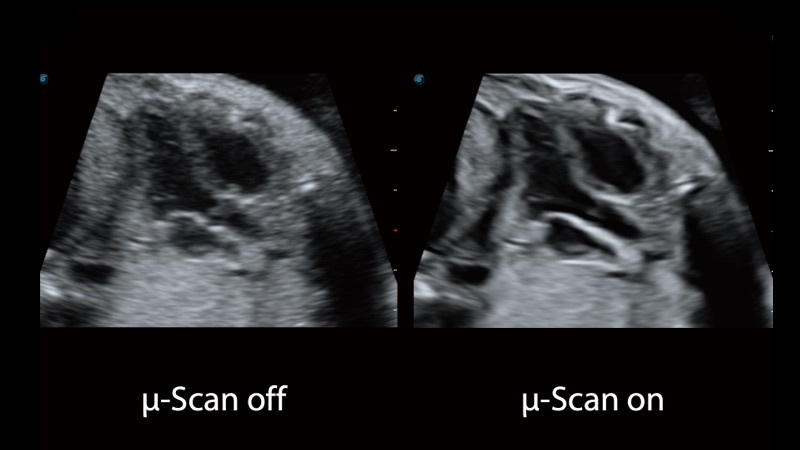

μ-Scan+新一代微米成像技术

新一代微米成像技术大大提高了器官和病变的可见性。高清对比度分辨率将抑制斑点噪声,同时保持真实的组织结构。